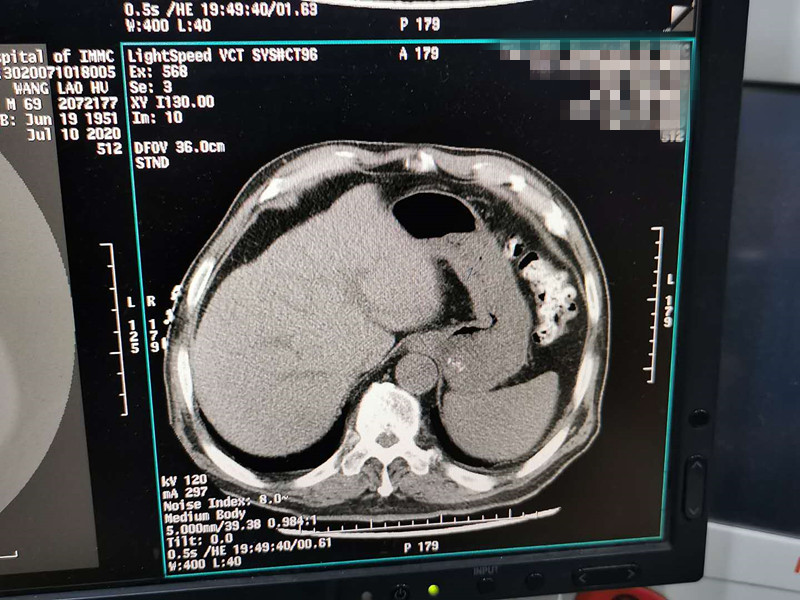

83岁肺部氩氦刀冷冻消融